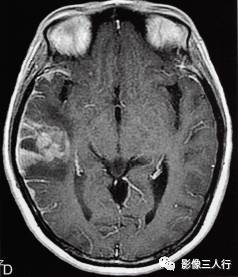

图1右颞叶横纹肌样脑膜瘤

A.T1WI横断面;B、C.T2WI横断面;D、E、F、G.增强横断面、矢状面、冠状面;H.HE×100

图1A:MRI T1WI示,右侧颞叶不规则形肿块,信号欠均匀,为稍低信号与小斑片状稍高信号混杂。其累及颞叶灰白质,界限欠清、边缘不整,大小约4.1cm×4.3cm×5.1cm。邻近脑沟脑裂变浅变平,周边脑实质受压。图1B、C:T2WI示,右颞不规则形肿块,信号欠均匀,为稍高信号与小斑片状略低信号混杂。灶周见带状高信号脑水肿。图1D~G:T1WI C示,右侧颞叶肿块呈不均匀的多个结节块状明显强化,邻近脑膜为线条状强化、增厚。